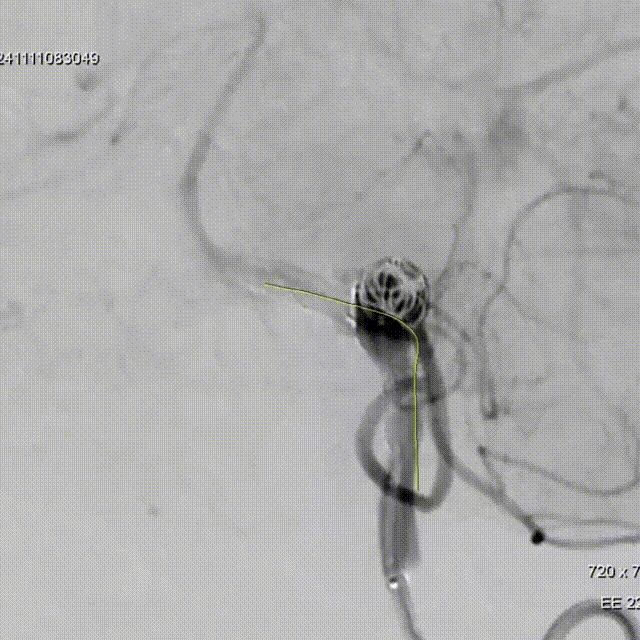

Tubridge Plus Case 2